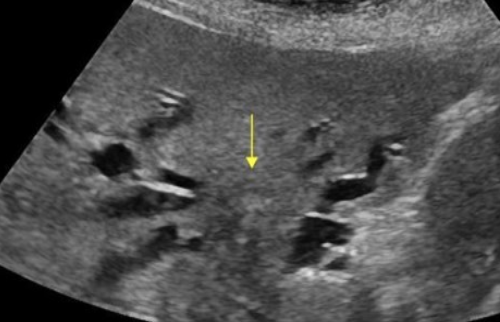

2D US: mixed pattern of echogenicity (hyperechoic from fibrosis to hypoechoic from inflammation), calcifications, normal to atrophic size, nodular surface, dilated/calcified pancreatic duct (> 3 mm), solid mass, thrombosis of splenic and portal vein

color doppler:

DDX: acute pancreatitis